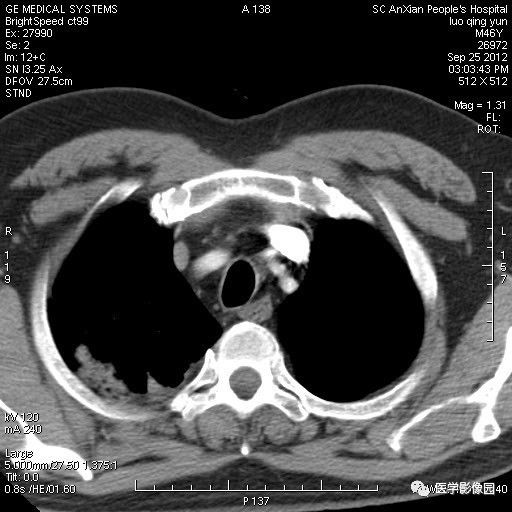

影像学表现:右上肺见不规则团块状高密度阴影,略有分叶级毛刺,边缘模糊,邻近胸膜增厚,增强扫描呈轻中度强化。

诊断结果:右上肺炎性假瘤

本病影像学表现无绝对特征性。单发多见,多位于肺表浅部位,多呈圆形或椭圆形,直径多在2-5cm或更大;多有假包膜,边缘多清晰光整,有时也毛糙,并可有分叶或毛刺;邻近胸膜局限性增厚、牵拉,病灶边缘呈桃尖样突起即桃尖征(尖端指向胸膜);增强扫描多呈中度均匀强化,持续时间较长。亦可显著强化。